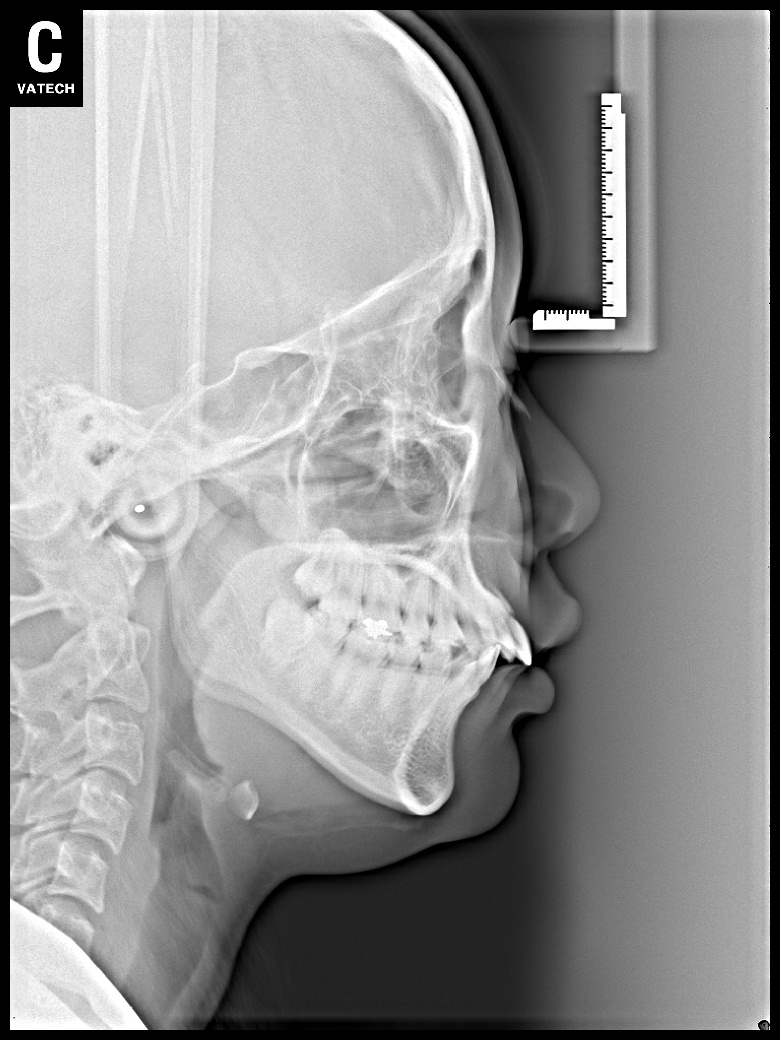

치료 전 사진입니다.